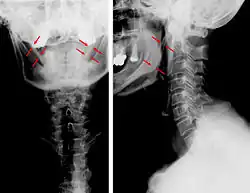

| Anteroposterior and lateral radiographs of cervical spine showing ossification of the stylohyoid ligament on both sides | |

CT scan, coronal section showing bilateral extended styloid process and stylohyoid ligament ossification (incidental finding) -

Imaging is important and is diagnostic. Visualizing the styloid process on a CT scan with 3D reconstruction is the suggested imaging technique.[13] The enlarged styloid may be visible on an orthopantogram or a lateral soft tissue X ray of the neck.